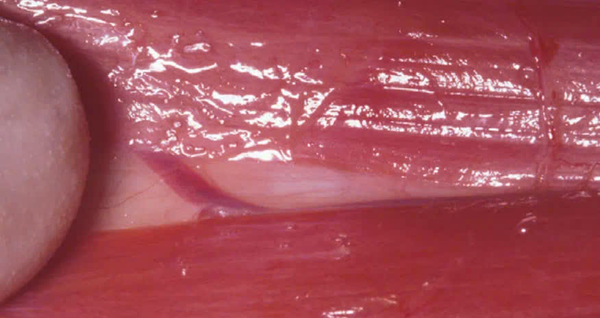

Ở giai đoạn này, điều quan trọng là xác định thực quản để tránh nguy cơ tổn thương. Mũi tên đen chỉ vị trí có thể tách vào một số lớp mô liên kết lỏng lẻo, giúp tiếp cận cơ dài cổ.

Sự khác biệt về màu sắc giúp phân biệt các cấu trúc này:

- Thực quản có màu hồng nhạt.

- Cơ dài cổ có màu đỏ sẫm.

Lúc này, dây thần kinh quặt ngược thanh quản cùng với khí quản được kéo sang một bên để tạo không gian cho phẫu thuật.